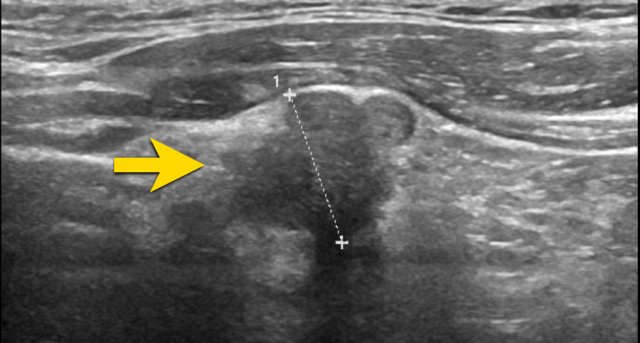

Very hypoechoic , i.e. 3 points in TI-RADS. Very hypoechoic , i.e. 3 points in TI-RADS.

A very hypoechoic lesion is more hypoechoic than normal muscle.

Notice that the tumor is more hypoechoic in comparison to the strap muscles (arrows).